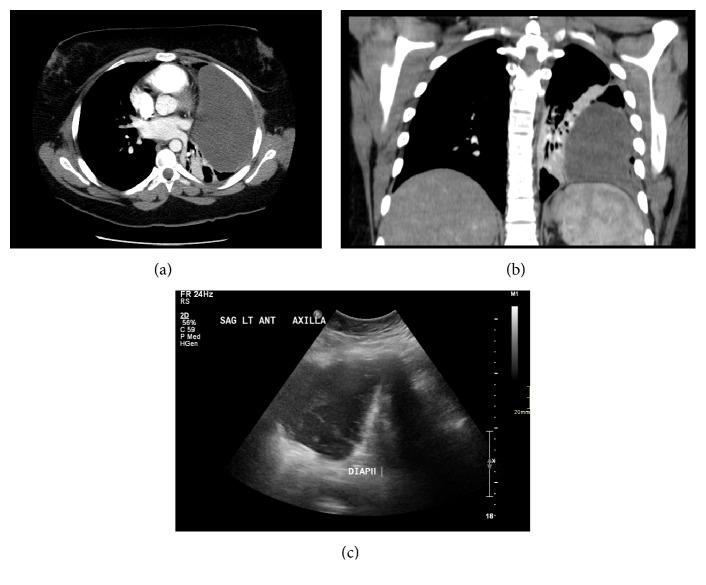

Mediastinal lymphangiomas are rare benign congenital malformations, but complications can occur, including infection, cystic hemorrhage, superior vena cava syndrome, airway compromise, and chylothorax. Radiologically, lymphangiomas are well-defined masses, with low attenuation ranging from simple to complex fluid and fat. They often encase adjacent mediastinal structures. We present a case of mediastinal lymphangioma in a young female, who presented with recurrent complex pleural effusions, initially thought to represent an empyema and/or necrotic mass. Despite surgical chest tube and interventional radiology drainage, fluid reaccumulated. Upon further review, the interventional and thoracic radiologist concurred that the complex collection was in fact predominantly extra pleural in location. The patient underwent partial resection after it was discovered intraoperatively that the extra pleural cystic mass was contiguous with and extended deeply into the mediastinum. Histopathology confirmed the diagnosis of lymphangioma.

纵隔淋巴管瘤是一种罕见的先天性良性畸形,但可能会出现并发症,包括感染、囊性出血、上腔静脉综合征、气道受压和乳糜胸。在影像学上,淋巴管瘤表现为边界清晰的肿块,密度较低,范围从单纯性到复杂性液体及脂肪。它们常包绕相邻的纵隔结构。我们报告一例年轻女性纵隔淋巴管瘤病例,该患者表现为复发性复杂性胸腔积液,最初被认为是脓胸和/或坏死性肿块。尽管进行了外科胸腔闭式引流和介入放射学引流,但液体仍再次积聚。经进一步检查,介入放射科医生和胸放射科医生一致认为,该复杂性积液实际上主要位于胸膜外。术中发现胸膜外囊性肿块与纵隔相连并深入纵隔后,患者接受了部分切除术。组织病理学确诊为淋巴管瘤。